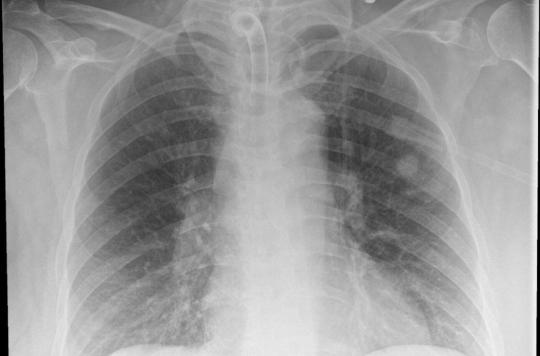

La radiographie pulmonaire Description La radiographie pulmonaire ou thoracique est un examen très couramment pratiqué Elle constitue souvent un examen de routine dans les visites d'embauche Il s'agit d'un examen radiographique qui prend tous les organes du thorax les poumons, la trachée, les bronches, la plèvre, les côtes, les clavicules.

La radiographie pulmonaire est essentiellement indiquée en cas de signes ou problèmes respiratoires toux persistante, expectorations, douleur du thorax ou de la poitrine (suite à un traumatisme par exemple). Since December 19, cases of coronavirus disease 19 (COVID19) have been emerging in Wuhan, Hubei Province, China, and the epidemic has swiftly spread to other parts of China and beyond 1 As of February 25, there were a total of 77 779 cases of diagnosed COVID19, 24 cases of suspected COVID19, 27 361 cured cases, and 2666 deaths from it in China, and there were 2464 cases of diagnosed. CHAPITRE 2 RADIOANATOMIE DU THORAX B Ghaye, C Beigelman, C Meunier, A Desir, X Boulanger, S Trogrlic and A Khalil Ce chapitre vise à rappeler l’anatomie normale du thorax et sa représentation radiologique, qu’il s’agisse de la radiographie thoracique, de la tomodensitométrie (TDM) ou de l’imagerie par résonance magnétique (IRM).

Title Microsoft Word parasitose_pulm Author omar Created Date 3/31/08 PM. Feuillets de Radiologie Vol 40 N° 5 p 349 Les pièges de la radiographie pulmonaire normale EMconsulte. La radiographie pulmonaire est recommandée en cas de troubles respiratoires, de quintes de toux persistantes accompagnées de fièvre, de douleurs thoraciques ou encore d’anomalies notées lors d’une auscultation pulmonaire classique au stéthoscope Une radio du thorax peut être demandée dans le cadre d’un bilan préopératoire.

A pulmonary consolidation is a region of normally compressible lung tissue that has filled with liquid instead of air The condition is marked by induration of a normally aerated lung It is considered a radiologic sign Consolidation occurs through accumulation of inflammatory cellular exudate in the alveoli and adjoining ducts The liquid can be pulmonary edema, inflammatory exudate, pus, inhaled water, or blood Consolidation must be present to diagnose pneumonia the signs of lobar pneumonia. Le bleu de méthylène impliqué dans l'amélioration de la mémoire à court terme MERCREDI 29 JUIN 16 Soyez le premier à réagir Selon une nouvelle étude publiée en ligne dans la revue "Radiology", une dose orale unique de bleu de méthylène augmenterait la mémoire à court terme, ainsi que l'attention. La radiographie pulmonaire est un examen qui permet de visualiser les poumons, la trachée, les bronches et la plèvre (feuillet qui entoure le poumon) Elle a pour but de détecter une infection, une inflammation, un cancer, une pleurésie ou encore un pneumothorax.

One year after, a fibroscopy showed a necrosis of the right main bronchus mucosae and the CT showed a radioinduced aneurysm protruding into the right inferior lobular bronchus The patient eventually died a few hours later. Parenchyme pulmonaire •«Trame » = vaisseaux Ø vasculaire plus large aux bases / sommets Ø bases / sommets = 2 / 1 en position debout •Symétrie de transparence et volume des 2 hémithorax bronches visibles de façon très proximale visible 15 mm de la paroi Parenchyme pulmonaire. La radiographie pulmonaire permet aux médecins de visualiser les organes intrathoraciques comme les poumons, la trachée, les bronches, le médiastin et la plèvre (Double feuillet qui recouvre le poumon).